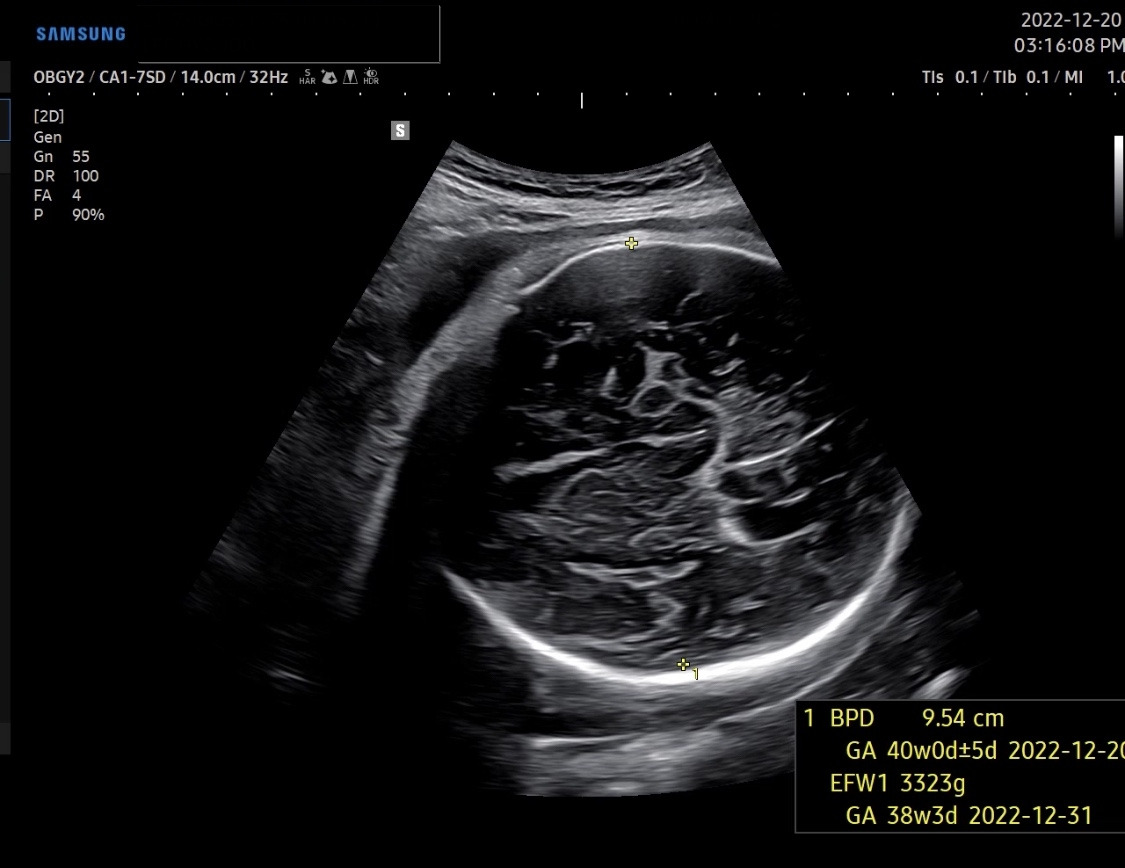

지난주에 못 만난 주치의 선생님, 오늘도 아기가 잘 크고 있는지 확인했다. 머리 사이즈는 여전히 9.5cm 정도에 머물러있었다. 우리 아기는 머리가 30주에 훌쩍 컸던 아이였나 보다. 아기마다 성장 속도에 차이가 있을 텐데 엄마아빠가 너무 성급히 걱정했던 것 같다. 예상 몸무게는 3.3kg 정도. 주치의 선생님은 이어서 내진을 해보셨고, 이미 1cm 정도 열려있는 자궁경부를 마사지하여 2cm 정도까지 열어두셨다고 하셨다. 내진으로 인해 집에 돌아가 오늘 밤에나 조만간 진통이 올 수도 있다고 하셨다. 그리고 며칠간 피가 좀 보일 수 있고, 생리 끝날 때쯤처럼 조금 묻어 나오는 정도면 괜찮지만 빨간 피가 생리대를 적실 정도면 병원으로 와야 한다고 하셨다.

KakaoTalk_20230101_104852065.jpg 어쩌면 마지막일 수도 있는 써니의 초음파 영상

그리고 이어서, 자궁경부가 잘 준비되는 중이고, 아기 크기도 적절하여 39주에 유도분만을 하기로 했다. 40주까지 기다릴 수도 있지만, 아기 머리가 더 크면 자연분만이 힘들어질 수도 있다. 나는 굳이 1월생을 고집하지 않았기 때문에, 39주 1일인 12월 26일 월요일에 유도분만을 하기로 했다. 나의 주치의 선생님은 의학적 사유가 특별히 있지 않는 이상 38주 6일 까지는 유도분만이나, 산모의 선택으로 인한 제왕절개를 하지 않는다고 하셨다. 그래서 나도 39주 이후로 예약을 잡았다. 남편의 연말 휴가일정도 고려해야 했고, 월요일 오전 정규 시간이 모든 의료진들이 가장 컨디션이 좋지 않을까 싶어서...